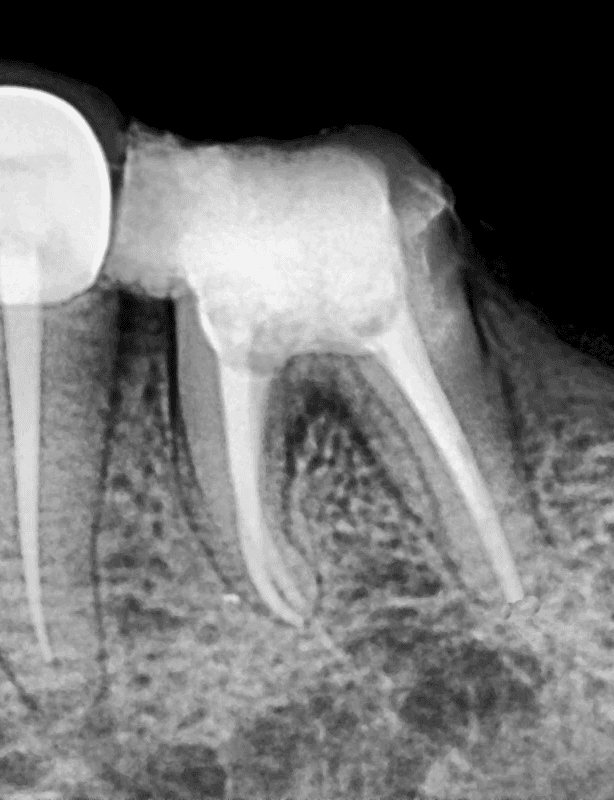

Before

After

Lower Molar

Severe Infection

Lower Molar Root Canal

Infection in the lower molar causing intense pain and swelling. Root canal treatment was performed to save the tooth.

Severe infection eliminated

Pain relief within 24 hours

Natural tooth saved